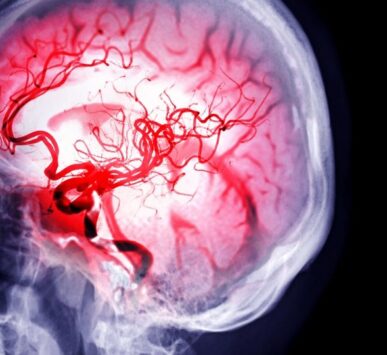

Dr. Seyhan Orak, tıp eğitimine Selçuk Üniversitesi Meram Tıp Fakültesi’nde başlamış ve temel tıp bilgisini burada edinmiştir. Tıp eğitimine olan bağlılığı, nörolojiye özellikle ilgisini çektiğinde onu Ege Üniversitesi Tıp Fakültesi Beyin ve Sinir Cerrahisi Anabilim Dalı’na yönlendirmiştir. Beyin ve sinir cerrahisi, karmaşık nörolojik sorunları ele alan ve cerrahi müdahaleler gerektiren bir alandır ve Dr. Seyhan Orak bu alanda uzmanlık eğitimi almıştır. Dr. Seyhan Orak’ın özel ilgi alanları arasında beyin tümörleri, omurilik tümörleri, bel fıtığı ve boyun fıtığı bulunmaktadır.

Beyin ve Sinir Sağlığınız Güvenilir Ellerde Gelişmiş Nöroşirürji Çözümleri ile Hassas Cerrahi, Kesin Sonuçlar.

Minimal İnvaziv Cerrahi Yaklaşımlar," "Nöromonitorizasyon (Ameliyat Sırasında Sinir İzleme)," "Görüntü Kılavuzlu Cerrahi (Nöronavigasyon)."